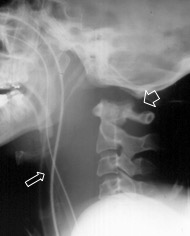

la dislocation craniocervicale

synonymes : luxation C0-C1, entorse occipito-cervicale

ces lésions étaient considérées classiquement comme hautement instables, rarement retrouvée chez les patients vivants mais plus souvent lors d’autopsie de traumatismes à haute cinétique (AVP Cf. ci-contre).

chez les survivants, on peut être orienté par une paralysie du VI (bilatérale éventuellement), une ecchymose du menton.

la radio standard montre un espacement entre condyles et atlas, une inversion du rapport de Powers, gun gonflement des parties molles rétro-pharyngées.

il peut exister une déchirure durale qui provoque la formation d’une méningocèle rétro-oesophagienne.

une fixation occipito-cervicale postérieure est nécessaire pour les lésions déplacées hautement instables.

depuis l’utilisation large de l’IRM, on a noté qu’en fait les lésions traumatiques occipito-C1 non déplacées ne sont pas si exceptionnelles. il faut y penser devant une hémorragie sous-arachnoïdienne du bas de la fosse postérieure. Le traitement de ces cas est orthopédique.